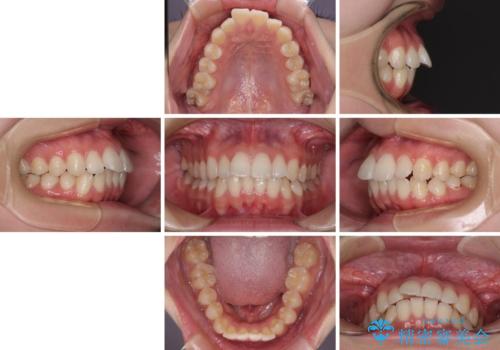

- 飛び出した上の前歯やデコボコを気にして来院された患者様です。

上下前歯の突出感とデコボコを気にして来院された患者様です。

インビザラインによる上下歯列の側方拡大と後方移動、必要に応じてIPR(歯と歯の間を削る)によりスペースの獲得により歯列を整えることとしました。

治療途中、出産や転居があり、2年ほど治療期間が長くなってしまいましたが、前歯の歯並びや飛び出した感覚を無事に改善させることができました。